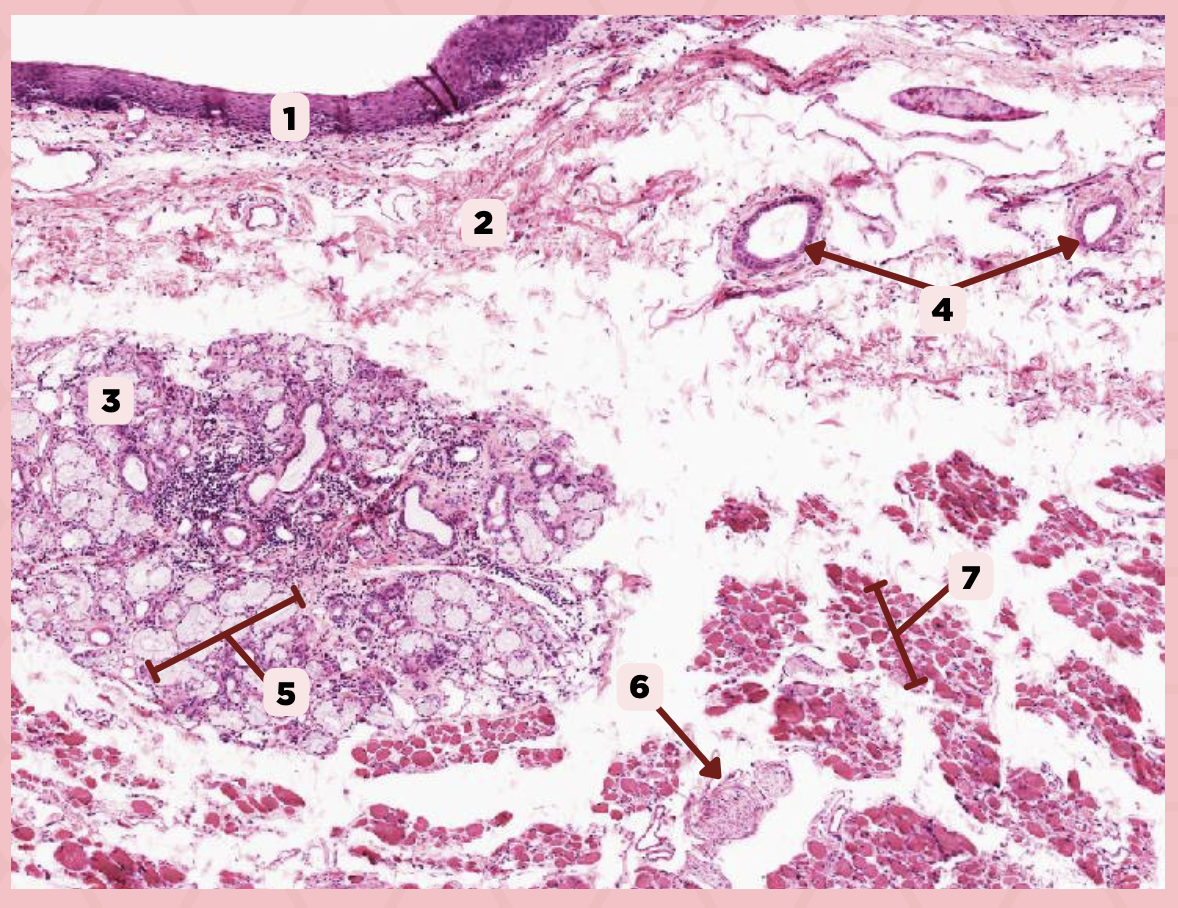

Cheek

Identify the specimen.

Mucosa

Identify the structure labeled as 1.

Lamina Propria

Identify the structure labeled as 2.

MALT

Identify the structure labeled as 3.

Blood Vessels

Identify the structure labeled as 4.

Buccal Glands

Identify the structure labeled as 5.

Nerve

Identify the structure labeled as 6.

Muscle Fascicles

Identify the structure labeled as 7.